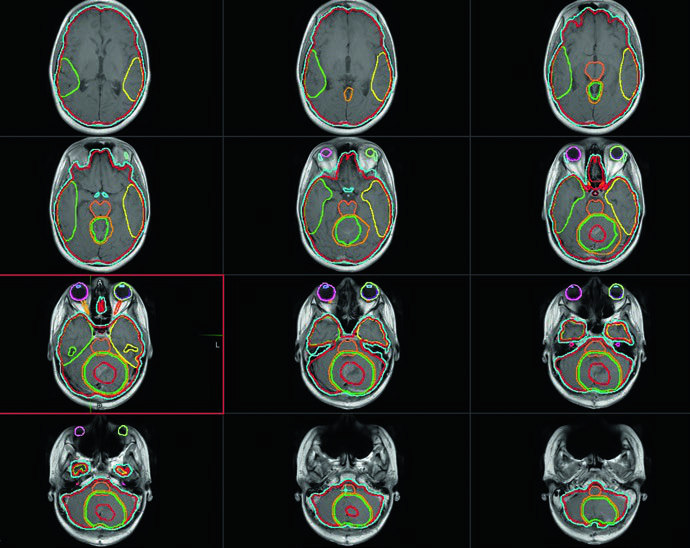

Volúmenes blanco para irradiación craneoespinal

El contorneo debe realizarse corte por corte en la TC de planificación. Las tablas siguientes resumen las definiciones recomendadas.

Volúmenes recomendados para irradiación craneoespinal (CSI)

| Volumen | Definición |

|---|---|

| GTV | Lecho tumoral incluyendo toda enfermedad residual macroscópica y paredes de la cavidad de resección en RM, más áreas de preocupación señaladas por el neurocirujano. Los defectos quirúrgicos por la vía de acceso no forman parte del GTV. |

| CTVCSI | Todo el volumen contenido por la duramadre en contacto con el líquido cefalorraquídeo, incluido el pseudomeningocele posoperatorio. En niños en crecimiento, incluye el cuerpo vertebral completo y el canal; en individuos adultos, solo el canal. |

| PTVCSI | CTVCSI + 3 a 10 mm según la confianza en el posicionamiento diario y la experiencia institucional. |

Fuente: Target Volume Delineation and Field Setup, 2nd Edition (Table 34.1)

Volúmenes recomendados para el boost del lecho tumoral

| GTV | Lecho tumoral con enfermedad residual macroscópica y paredes de la cavidad en RM, más áreas identificadas por el neurocirujano. |

| CTVboost | GTV + 1 a 1,5 cm de margen anatómicamente confinado. Excluir barreras de diseminación como el tentorio. Limitar el margen en el tronco cerebral a 2–3 mm en áreas de contacto tumoral. |

| PTVboost | CTVboost + 3 a 5 mm basado en imágenes diarias y experiencia institucional. |

Fuente: Target Volume Delineation and Field Setup, 2nd Edition (Table 34.2)

Volúmenes para boost de fosa posterior completa

| GTV | Lecho tumoral con enfermedad residual, paredes de la cavidad y áreas señaladas por el neurocirujano. |

| CTVFP | Toda la fosa posterior incluyendo el tronco cerebral completo. Límites: base del cráneo anteriormente, tentorio superiormente, foramen magno inferiormente. El hueso del cráneo restringe posterior y lateralmente. |

| PTVFP | CTVFP + 3 a 5 mm según frecuencia de imagen y experiencia institucional. |

Fuente: Target Volume Delineation and Field Setup, 2nd Edition (Table 34.3)